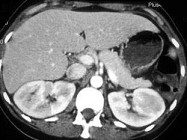

- 单项选择题如图所示,根据这两个时相分析, 最可能的诊断是 ( )

A、肾淋巴瘤

B、急性肾盂肾炎

C、肾梗死

D、肾癌

E、肾囊肿